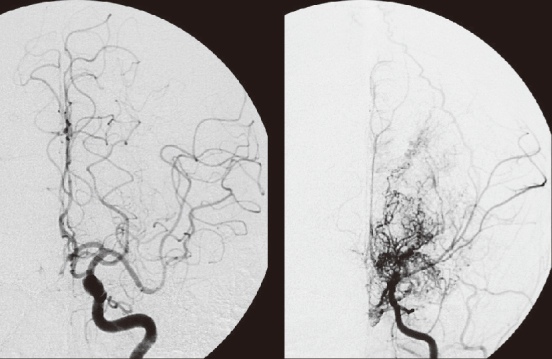

모야모야병(Moyamoya Disease)은 뇌의 주요 혈관인 내경동맥이 점차 좁아지거나 막혀, 뇌로 가는 혈류가 줄어들고, 이를 보상하기 위해 뇌 안에 가느다란 새로운 혈관이 형성되는 희귀 질환입니다. 이 혈관들은 뇌혈관조영술 영상에서 연기처럼 퍼지는 모습으로 보이는데, 일본어로 ‘모야모야’(もやもや)는 안개가 자욱한 모양을 의미합니다. 이러한 특이한 혈관 소견 때문에 ‘모야모야병’이라는 명칭이 붙었습니다. 주로 "소아기와 청장년기(20~40대)"에 발생하며, 뇌출혈, 뇌경색, 일과성 허혈 발작 등을 유발할 수 있어 조기 발견과 치료가 매우 중요합니다.

③ 뇌혈관조영술(DSA)

- 진단의 골드 스탠다드

- 정맥 또는 동맥에 조영제를 주입한 후 뇌 전체 혈관망을 실시간으로 촬영

- 모야모야 혈관의 특성적인 모습(연기처럼 퍼짐)을 확인할 수 있음